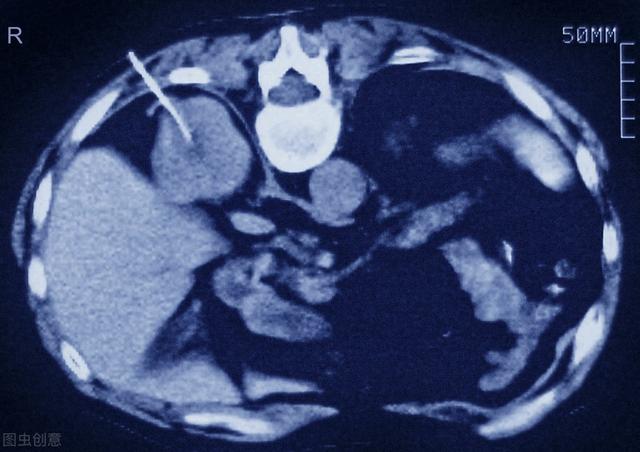

Scanner des biopsies rénales

Biopsie rénale pour clarification pathologique

Outre les biomarqueurs dérivés du sang et de l'urine, la biopsie rénale peut être un moyen efficace de prédire la régression de la néphropathie diabétique. Cependant, la biopsie rénale est un test invasif et très peu pratique dans la pratique clinique.